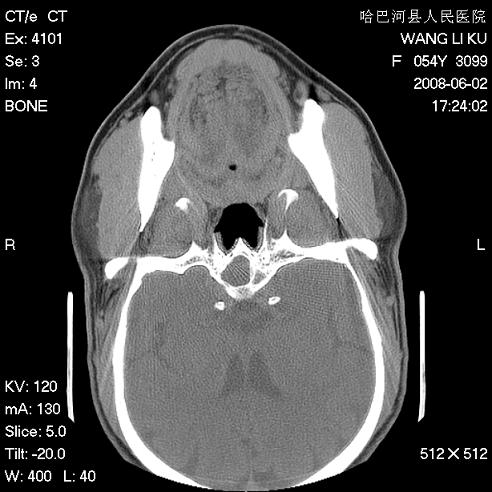

标题: CT13803:反复性鼻塞、流涕一年余 [打印本页]

标题: CT13803:反复性鼻塞、流涕一年余

副鼻窦炎,右上额窦积脓。左眼肌锥内见致密影,视神經受压

1.全组副鼻窦炎2.双侧上颌窦积液

1)全副鼻窦炎(左侧上颌窦黏膜下囊肿或息肉)。2)左眼眶肌锥内不规则小结节状软组织密度影;考虑为小血管瘤可能。建议行ct增强扫描检查。

全组副鼻窦炎,左侧肌锥内不规则形软组织肿块影,与眼外肌密度相当,左侧视神经受压,肿块与视神经及眼外肌分界清晰,眼外肌无增粗,眶壁无破坏,球后脂肪间隙不模糊,考虑良性改变,小血管瘤或神经源性肿瘤可能,建议增强扫描。

谢谢,增强扫描做了,眶内病灶与海绵窦同步明显强化,血管瘤